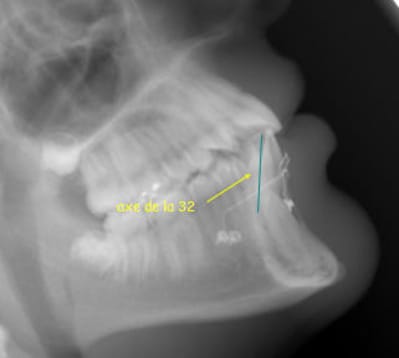

la canine comme le montre très bien ta radio de profil

est en plein milieu de la symphyse et est plantée entre 2 apex d'incisive

elle n'est donc ni Vestibulaire ni lingual puisqu'elle est au milieu

mais comme il est impossible d'aller la chercher en lingual à ce niveau, elle est pour toi forcement vestibulaire

cela dit par rapport aux couronnes des incisives dans le sens antéro-posterieur la couronnes de la canine est bien plus lingual puisqu 'au niveau des apex

c'est pourquoi elle est tres élargie car en arriere du plan de coupe passant par les couronnes des incisives mandibulaires !

la tele n'est pas trompeuse du tout elle est on ne peut plus juste

dans le sens antero postérieur :

le point B est en arriere des couronnes des incisives

la couronnes de la canine est donc en arriere du point B puisque dans l'os et donc forcement en arriere

c'est un notion de plan de coupe verticale.

sur la photo la face Vestibulaire de la canine est belle et bien arriere des couronnes des incisives max et mand

lorsque l'on prend un panoramique le patient se tient debout

la verticale est donc la verticale du patient (a peu de chose pres), le bord des incisives dans la fourchette de de la pano

et non pas tete completement penché en arriere comme tu le simules en faisant une rotation de l'image

car le referentiel c'est la relation de position entre le tube panoramique et la position du patient dans la machine

ainsi le patient est debout et la zone de tomographie est la zone verte comme situé sur mon image (remise dans les conditions reelles de prise du cliché)

par consequent, MOI je dis que la couronne de la canine est situé en arriere de la couronne des incisives mandibulaires ( par rapport à la verticale comme defini precedement) ce que qui fait que la règle enoncé au debut reste juste

et que toi tu dis que la dent est Vestibulaire puisque situé en avant des racines (le contraire étant est assez rare, tu en conviendras)